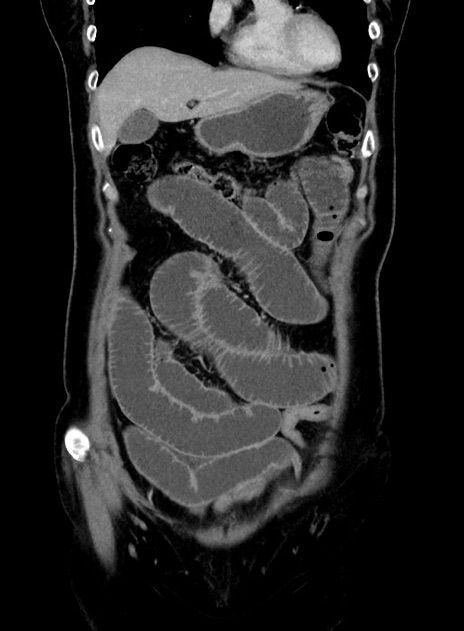

横断像

【症例】 60歳代女性

【主訴】むかつき、みぞおちの痛み

【現病歴】3日前よりむかつきがあり、食事がとれない。

【既往歴】糖尿病

【身体所見】発熱なし、心窩部圧痛軽度あるも、腹膜刺激症状なし。

【データ】WBC 7400、CRP 1.92